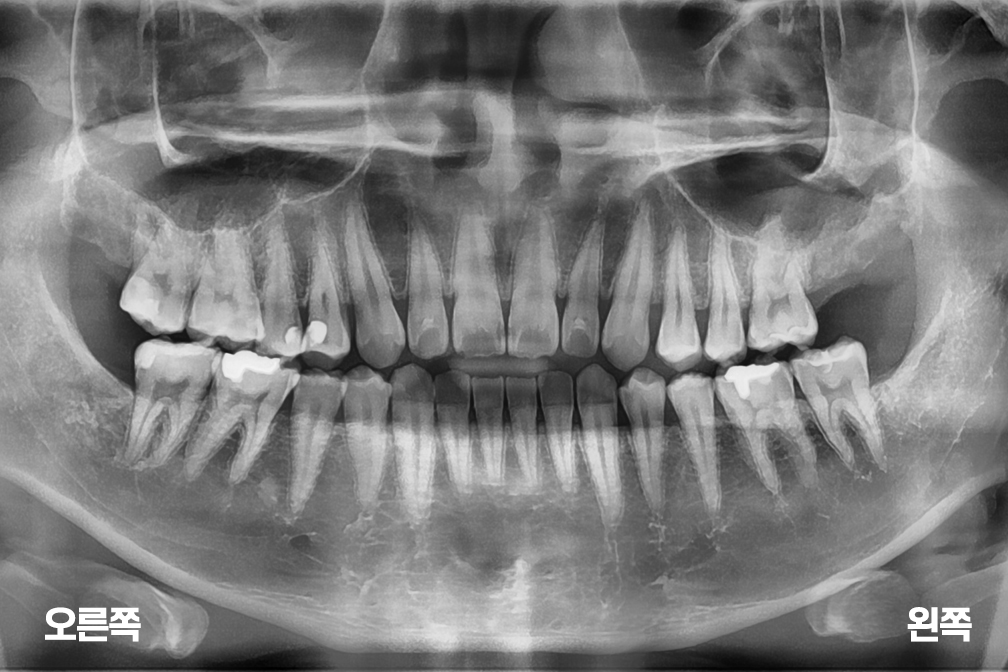

사랑니발치 사랑니 4개 발치

사랑니 발치